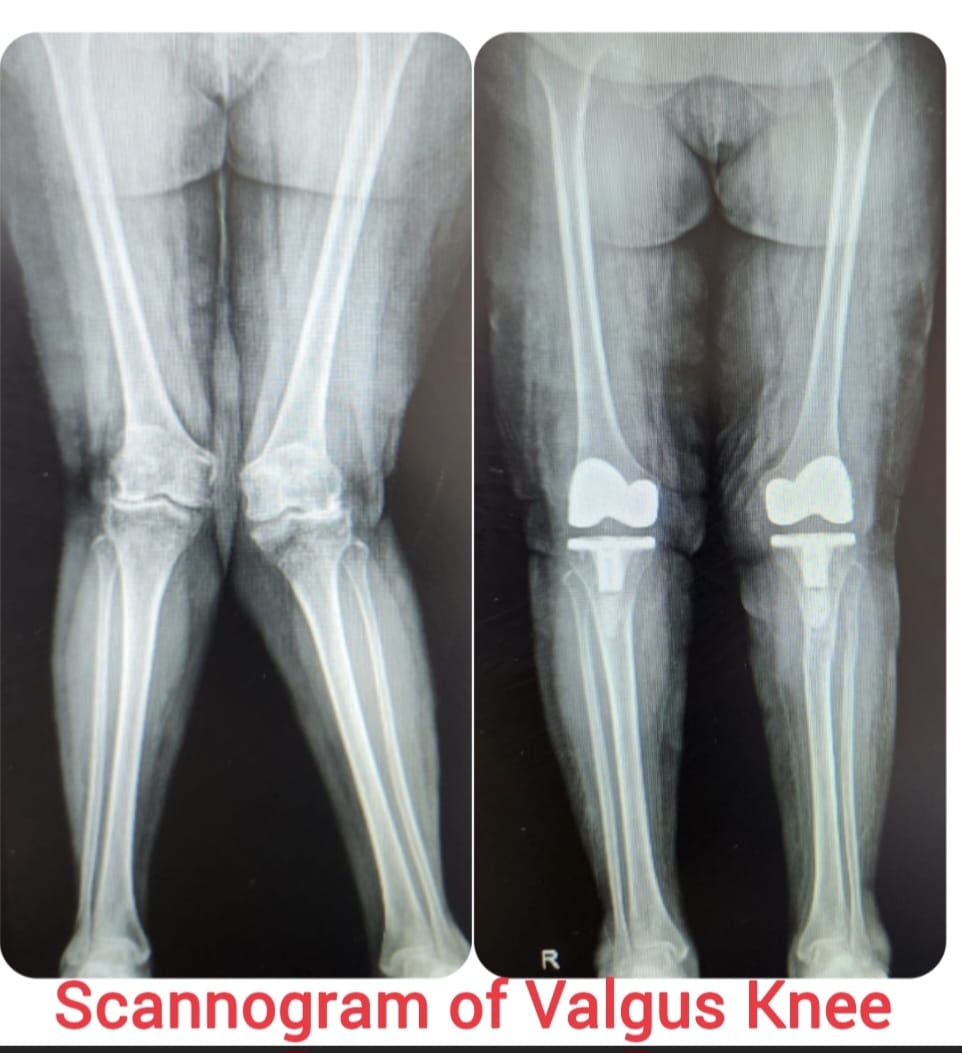

Knee replacement, also known as knee arthroplasty, is a surgical procedure performed to relieve chronic knee pain and restore joint function in patients suffering from advanced arthritis, severe joint damage, or deformities. The procedure involves replacing damaged cartilage and bone surfaces with durable artificial implants that restore smooth knee movement.

Knee arthroplasty is carefully planned based on the patient’s age, activity level, degree of joint damage, and overall health. Modern surgical techniques and advanced implant designs allow improved alignment, stability, and long-lasting outcomes with reduced postoperative discomfort.